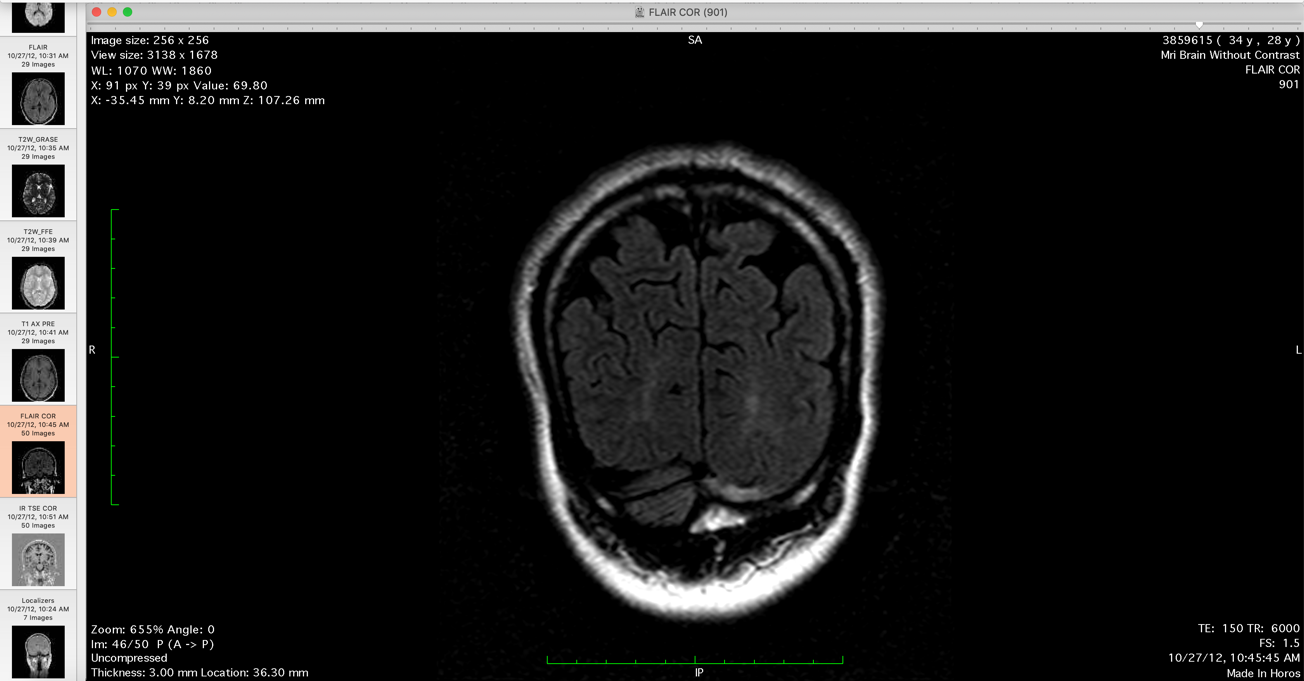

Pia: So you have MRI scans with you?

Me: Yup I have the MRI scans with me.

So that shows posterior brain [lesions], and you can see.... Its mostly the occipital region. And what typically happens is that.... if

Pia: So where is the lesion?

[these are the clear lesions shown to Dr. Pia, which he deludedly professes not to be able to see its clinical fraud in statement]

Me: Keep going back. So there you go, these intensities here.

Pia: Lets look at the transversal slides.

Me: Its depends on the, what I did is that I had the radiologist do a comparison of the different MRIs and then he noted where these intensities.

Pia: So these are the newest ones.

Me: No these aren't the newest.

Pia: Show me the newest.

Me: So, this is the new, newer. This would show the posterior intensity sometime it will show some central intensity....

Pia: Contrast enhanced in any one of time? [Dr. Pia makes a misstatement]

Me: Hmm, they have. The contrast is the T1 images hmm, but....

Pia: Do you have any spinal lesions?

Me: Yup, I do as well. I have the spinal MRI, just have to move the mouse to the right.